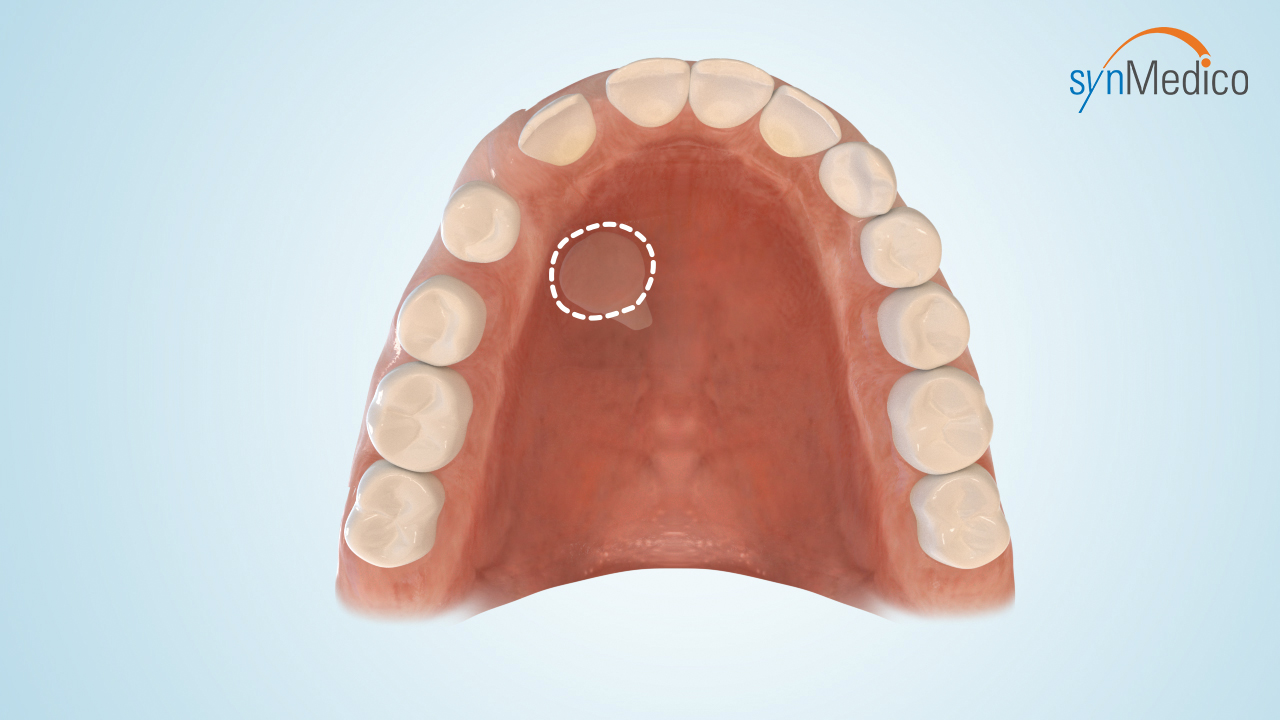

Freilegung von Zähnen

Gelegentlich verbleiben Zähne in der Wachstumsphase im Kiefer, da eine Blockade durch Nachbarzähne den Durchtritt verhindert. Durch eine kombinierte Behandlung mit den Techniken der Kieferorthopäde und der Kieferchirurgie können solche Zähne in die Zahnreihe eingestellt werden.